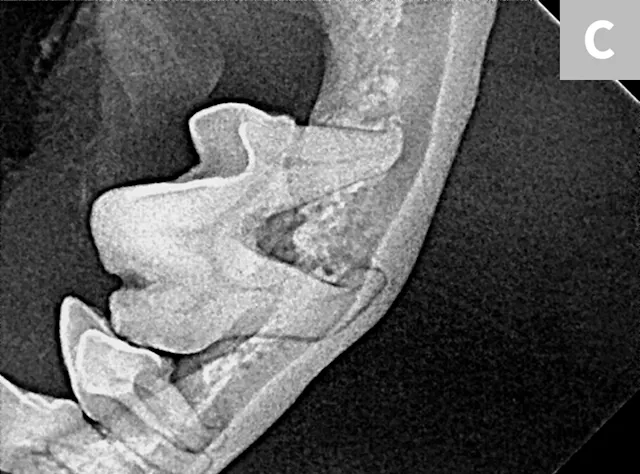

FIGURE 6

Iatrogenic fracture of the left rostral mandible after extraction of the left mandibular canine tooth (A; arrows). Same patient with iatrogenic jaw fracture after extraction (B); significant bone loss from periodontal disease was present, which contributed to this complication. Dilacerated root of the left mandibular first molar in a small-breed dog (C). The first molar in these breeds is often very large as compared with the width of the mandible. The hook on the mesial root can make extraction more challenging.

Small-breed dogs have a high first molar:mandibular height ratio, which increases the risk for fracture in cases of periodontal disease.14 In such cases, the roots can also be dilacerated (ie, there is an abnormal bend, hook, or overall shape to the root[s]); the tooth may have significant bone loss and appear to be an easy extraction, but the hook on the end of the root tip often makes removal much more difficult (Figure 6C).